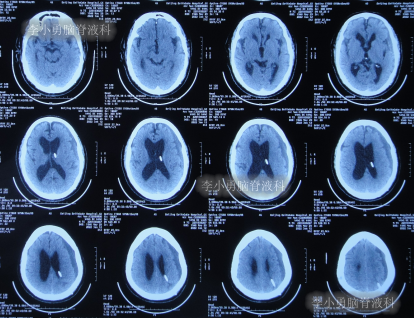

2020年10月29日(发病已8年),因症状一直没有得到改善且呈进行性加重趋势,查头部核磁示脑积水(图-1)。

图-1:2020年10月29日头部核磁